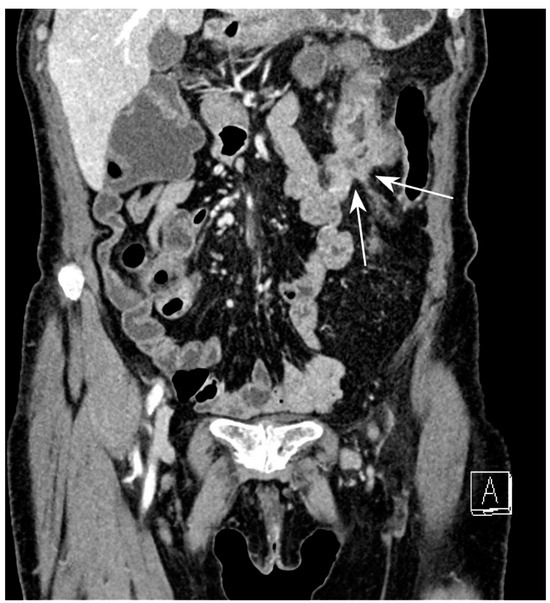

5.1. Active Subtype